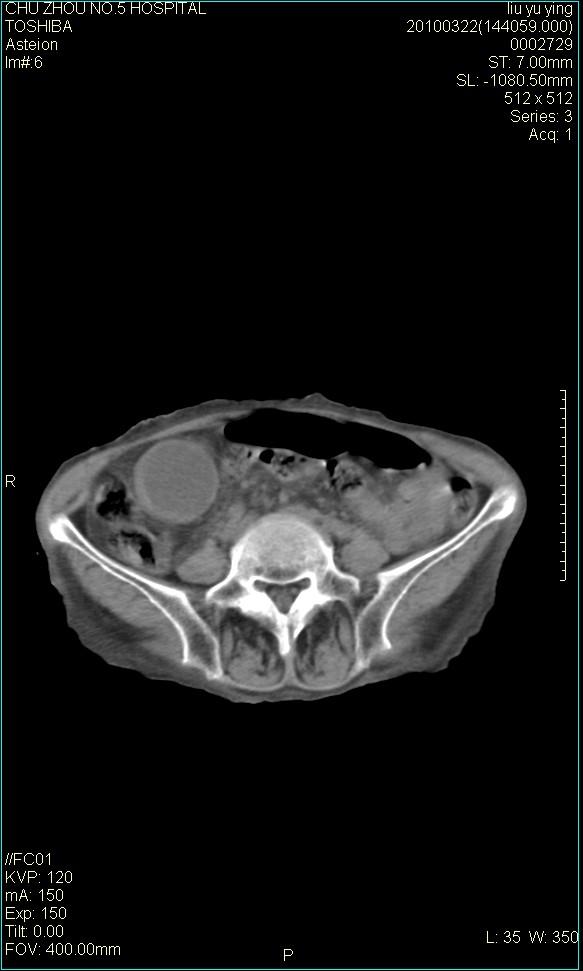

以下是引用科室第一人在2010-3-23 6:50:00的发言:[br]胆总管下段梗阻,多为肿瘤性病变,巨形胆囊,胆囊炎胆囊窝积液。[br]双侧胸腔积液,右降

以下是引用随光逐影在2010-3-23 8:12:00的发言:[br]1)胆系低位梗阻(肝内外胆管扩张,胆囊增大),原因待查。2)胆囊炎。3)双侧少量胸腔积液。4)降主动脉迂曲。